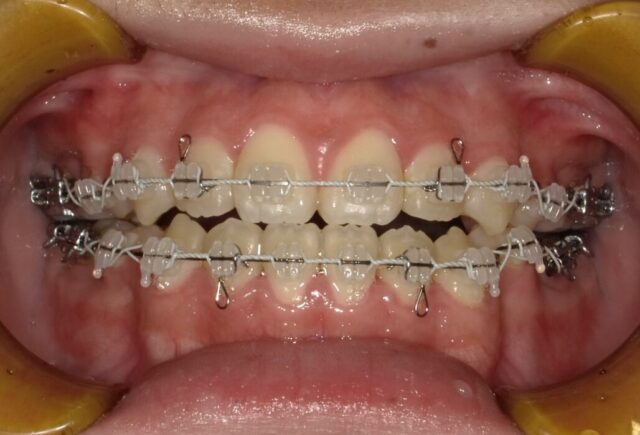

≪正面観≫

2023年5月

2023年6月

2023年7月

2023年8月

2023年9月

2023年10月

2023年11月

2023年12月

2024年1月

2024年2月

2024年3月

2024年4月

2024年5月

2024年6月

2024年7月

2024年8月

2024年9月

2024年10月

2024年12月

2025年1月